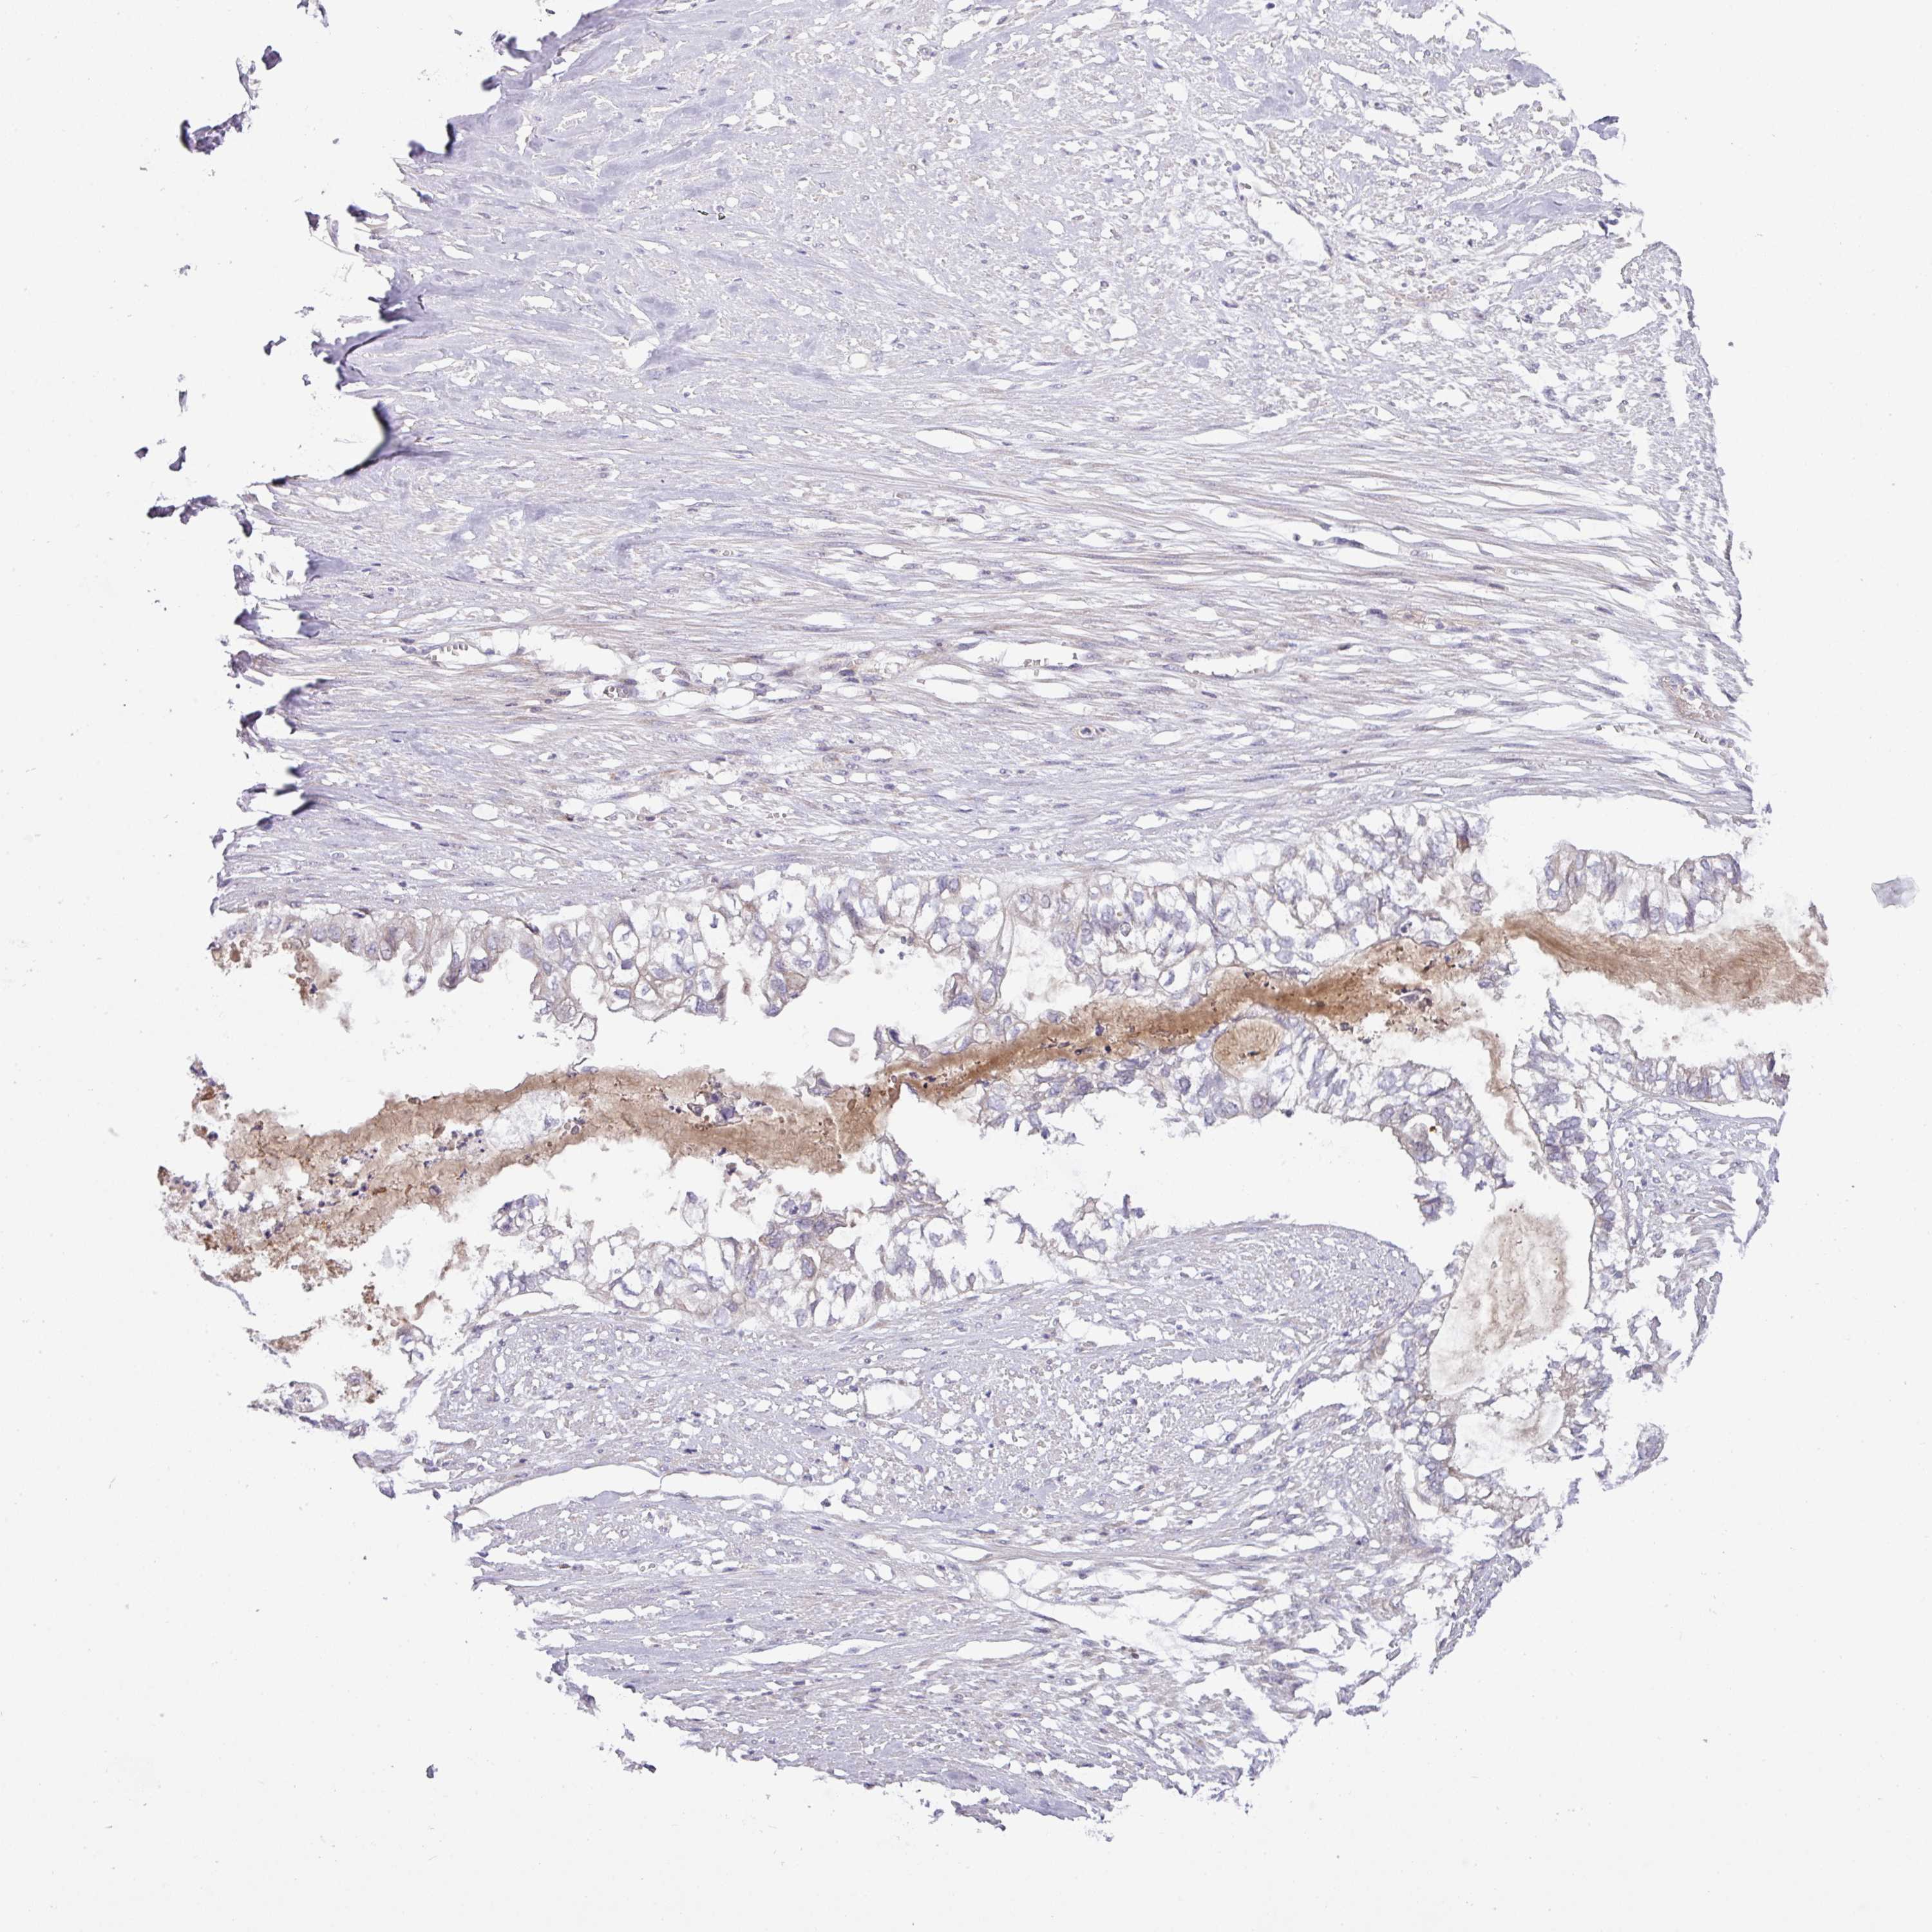

OVARIAN CANCER - Protein expressioni

A mouse-over function shows sample information and annotation data. Click on an image to view it in a full screen mode. Samples can be filtered based on level of antibody staining by selecting one or several of the following categories: high, medium, low and not detected. The assay and annotation is described here.

Note that samples used for immunohistochemistry by the Human Protein Atlas do not correspond to samples in the TCGA dataset.

Antibody stainingi

Antibody staining in the annotated cell types in the current human tissue is reported as not detected, low, medium, or high, based on conventional immunohistochemistry profiling in selected tissues. This score is based on the combination of the staining intensity and fraction of stained cells.

Each image is clickable and will lead to virtual microscopy that enables deeper exploration of all samples and also displays staining intensity scores, fraction scores and subcellular localization as well as patient and tissue information for each sample.

Antibody HPA051421

Antibody HPA054639

Cystadenocarcinoma, serous, NOS

Cystadenocarcinoma, mucinous, NOS

Adenocarcinoma, NOS

Carcinoma, endometroid